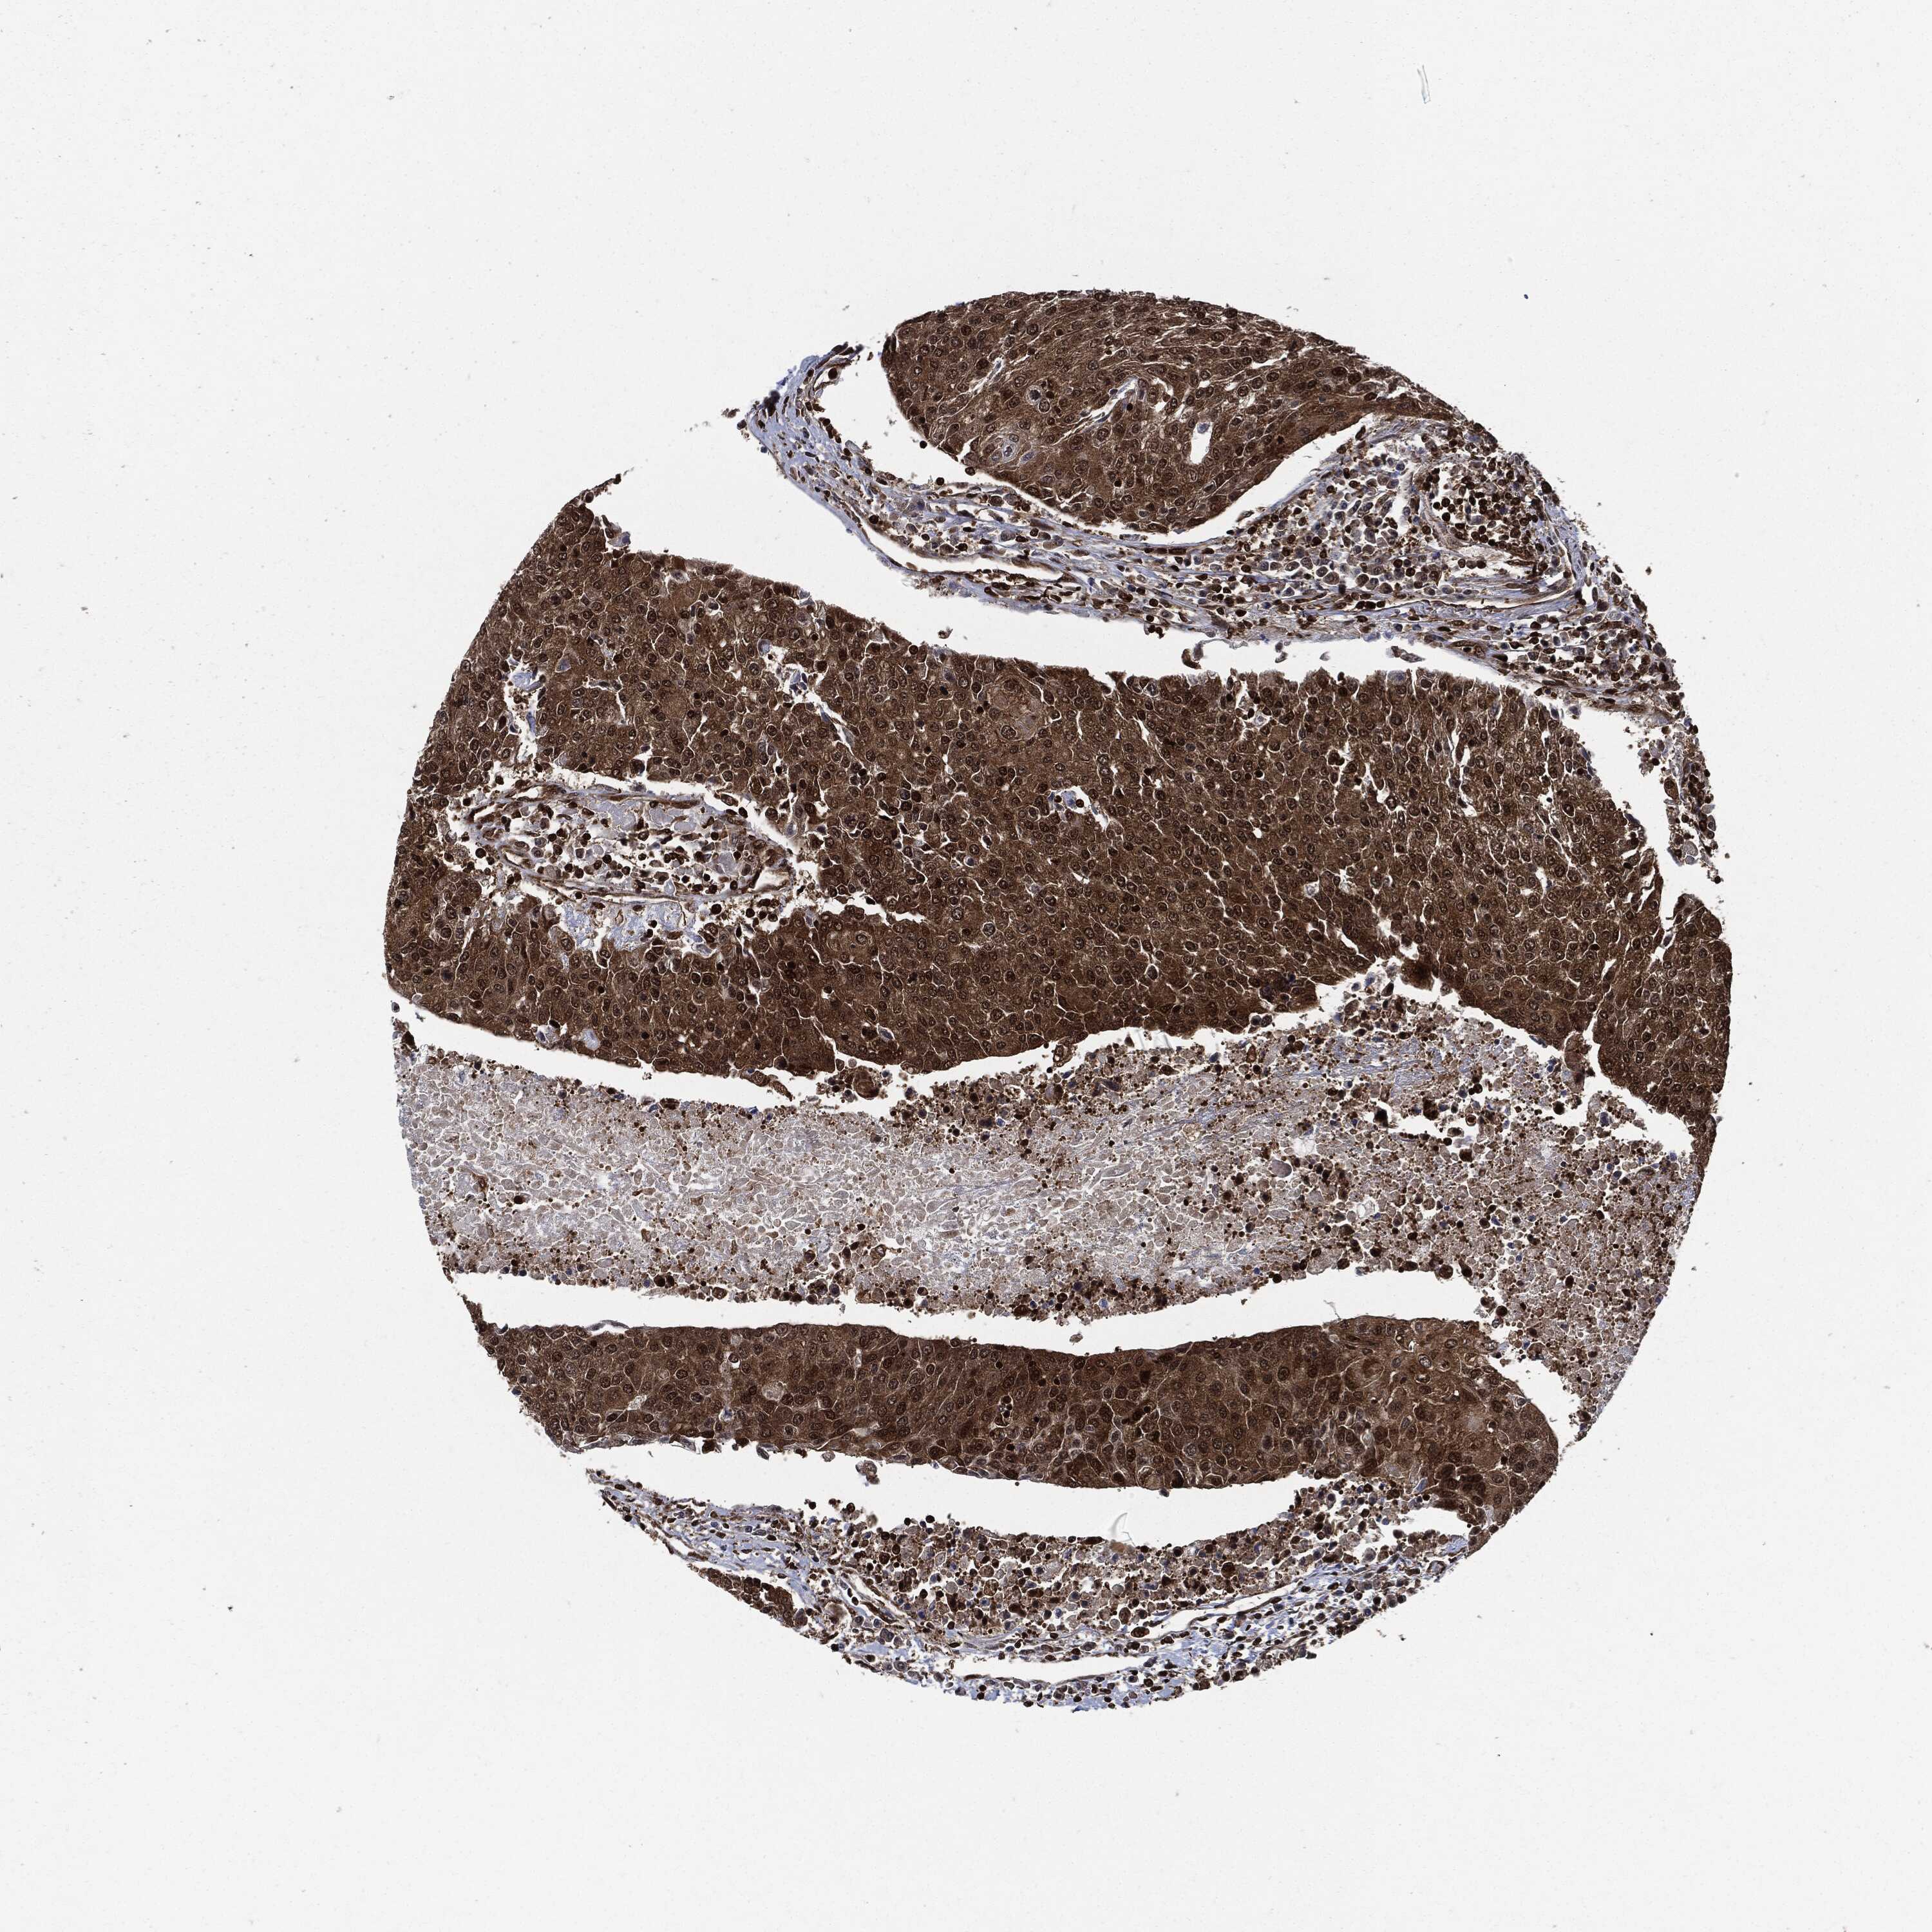

UROTHELIAL CANCER - Protein expressioni

A mouse-over function shows sample information and annotation data. Click on an image to view it in a full screen mode. Samples can be filtered based on level of antibody staining by selecting one or several of the following categories: high, medium, low and not detected. The assay and annotation is described here.

Note that samples used for immunohistochemistry by the Human Protein Atlas do not correspond to samples in the TCGA dataset.

Antibody stainingi

Antibody staining in the annotated cell types in the current human tissue is reported as not detected, low, medium, or high, based on conventional immunohistochemistry profiling in selected tissues. This score is based on the combination of the staining intensity and fraction of stained cells.

Each image is clickable and will lead to virtual microscopy that enables deeper exploration of all samples and also displays staining intensity scores, fraction scores and subcellular localization as well as patient and tissue information for each sample.

Antibody HPA007925

Antibody HPA011212

Antibody CAB003759

Antibody CAB080290

Urothelial carcinoma, Low grade

Urothelial carcinoma, High grade